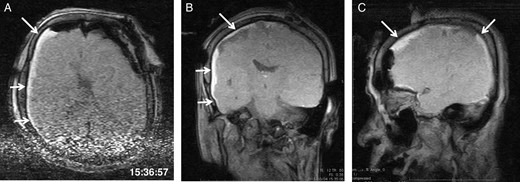

The third intraoperative magnetic resonance images after intubation, axial (A), coronal (B) and sagittal (C) T1-weighted scout images show acute right-sided subdural hematoma (arrows), contralateral to the site of the craniotomy. The time of scan is superimposed.

General anaesthesia was induced. Following left frontal craniotomy and dural incision, the first iMRI was performed (Fig. 1 ). One hundred fifty-eight minutes from induction, the patient regained consciousness after all anaesthetics were ceased. Tumour resection was performed with free conversation. However, after 143 min of surgery under the awake condition, the patient came to complain of excessive sleepiness though she could respond to verbal commands. Electrocorticogram (ECoG) did not detect after-discharge. The tumour was successfully removed en bloc fashion. Progressive brain swelling was not observed. The second iMRI was commenced 182 min into the awake phase (Fig. 2). Thirteen minutes from the beginning of the second iMRI scanning, the patient did not respond to noxious stimuli. When the patient was removed from the gantry, she was unconscious and had stopped spontaneous breathing. Her pupils were isocoria and did not dilate. Neither epileptic seizure nor anaphylactic reaction occurred. The peripheral oxygen saturation was not measurable, but cardiac instability or signs of vomiting were not observed. We decided to discontinue the operation under the awake status. No electrolyte imbalance or hypoglycaemia was observed. Subsequently performed iMRI identified a thin subdural haematoma in the contralateral side (Fig. 3). The fourth iMRI confirmed that most of the haematoma was evacuated following right frontal craniotomy.